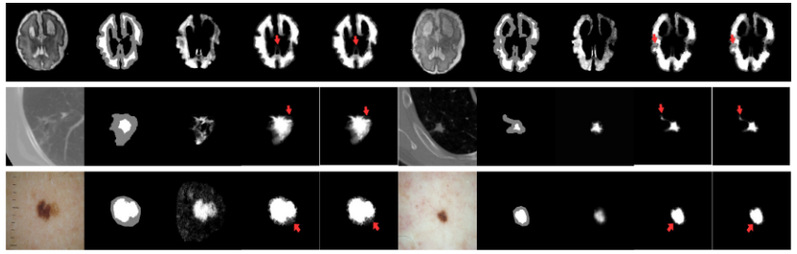

实验结果表 2表明,在仅提供Trimap的弱先验条件下,微搜索进化优化医学图像抠图算法在均方误差和梯度误差上,优于大多数对比方法。可视化结果(图 4)也显示,该方法能更准确地恢复前景与背景极其相似的模糊边缘区域。 表 2 弱先验测试场景中抠图预测指标对比

图 4 有无微搜索策略的抠图预测结果可视化对比